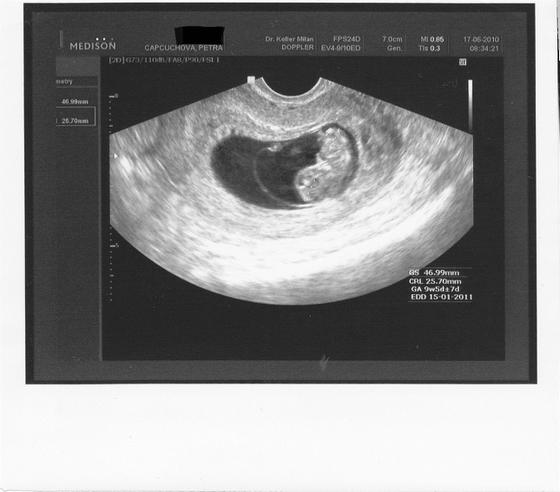

18.6.2010 Kontrolní utz, potvrzen syndrom mizejícího dvojčete. Druhý se má čile k světu, pan doktor mi pustil jeho srdíčko, tak jsem slyšela, jak krásně pravidelně a silně mu bije srdíčko! Byl to nádherný zažitek, ze kterého jsem měla slzičky štěstí. Bobísek jež by měl odpovídat 9+2tt je o tři dny dopředu čili 9+5tt a měří 2,5 cm.